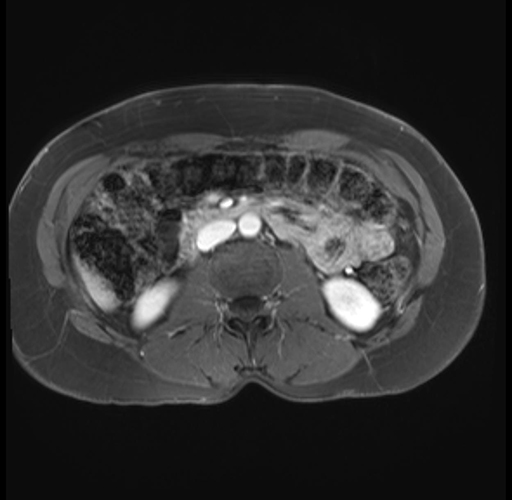

Imaging Analysis

Look through the patient's CT scan to identify any areas of concern for the necessary procedure.

Based on your CT findings, which issue(s) are present and would give reason for "planned slowing down moment(s)" in this case?

Considering a standard distal pancreatectomy procedure, what step(s) of the operation would you do differently in this case?